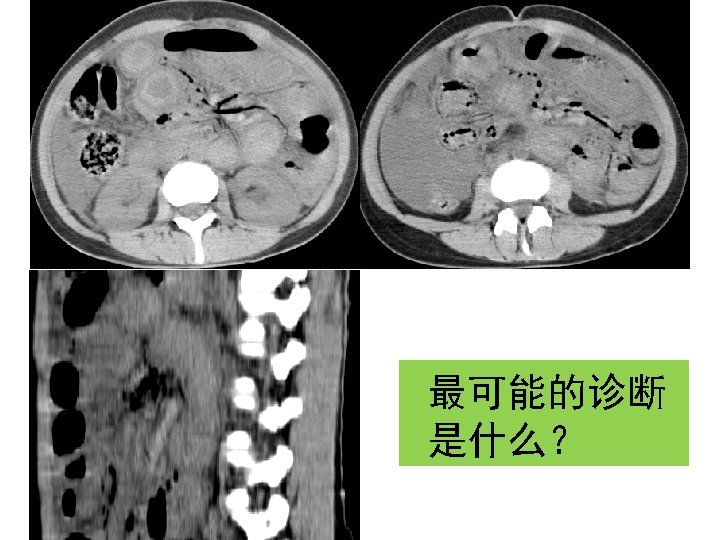

Target sign A 27 -year-old male presented with abdominal pain of 10 hours duration

Target sign A 27 -year-old male presented with abdominal pain of 10 hours duration 肠系膜上静脉血栓形成

粘连性肠梗阻 fat notch sign